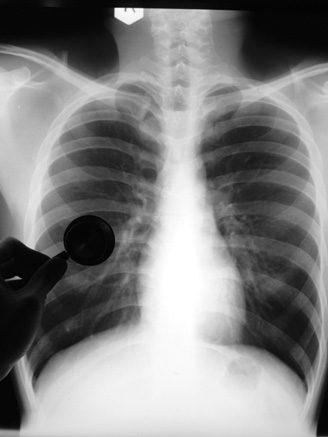

SRI researchers conducted a series of studies that modeled the pathogenesis of human respiratory diseases such as emphysema and chronic obstructive lung disease. The studies proved that these diseases were caused in humans by common contaminants of air derived from industrial and automobile exhausts and tobacco smoke. The results were fundamental to national and international efforts in setting allowable limits of nitrogen oxide and ozone contents in industrial exhausts and indoor air-quality standards.